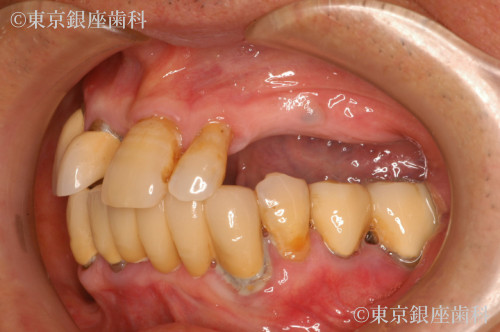

重度歯周病、義歯不適合による咬合障害をワンデイインプラントで改善した症例

Before

入れ歯が痛くて入れられない。噛めないので食事を丸のみにしているため胃の調子が悪い。

全体的に歯周病が進行していること、咬合改善を希望されていることから残存歯を全て抜歯してワンデイインプラントにすることにした。